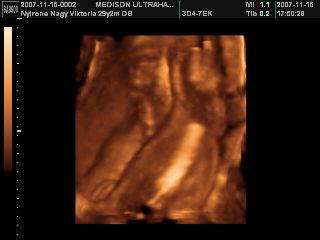

És van egy kis elmaradásom, mikor 4d-n voltunk nem tettem fel képeket, de most megvannak, szóval Eszti baba 25+3-nál:

és ennyi, mert ennyit láttunk összesen, hiába sétáltam, böködtem, nem mozdult el!